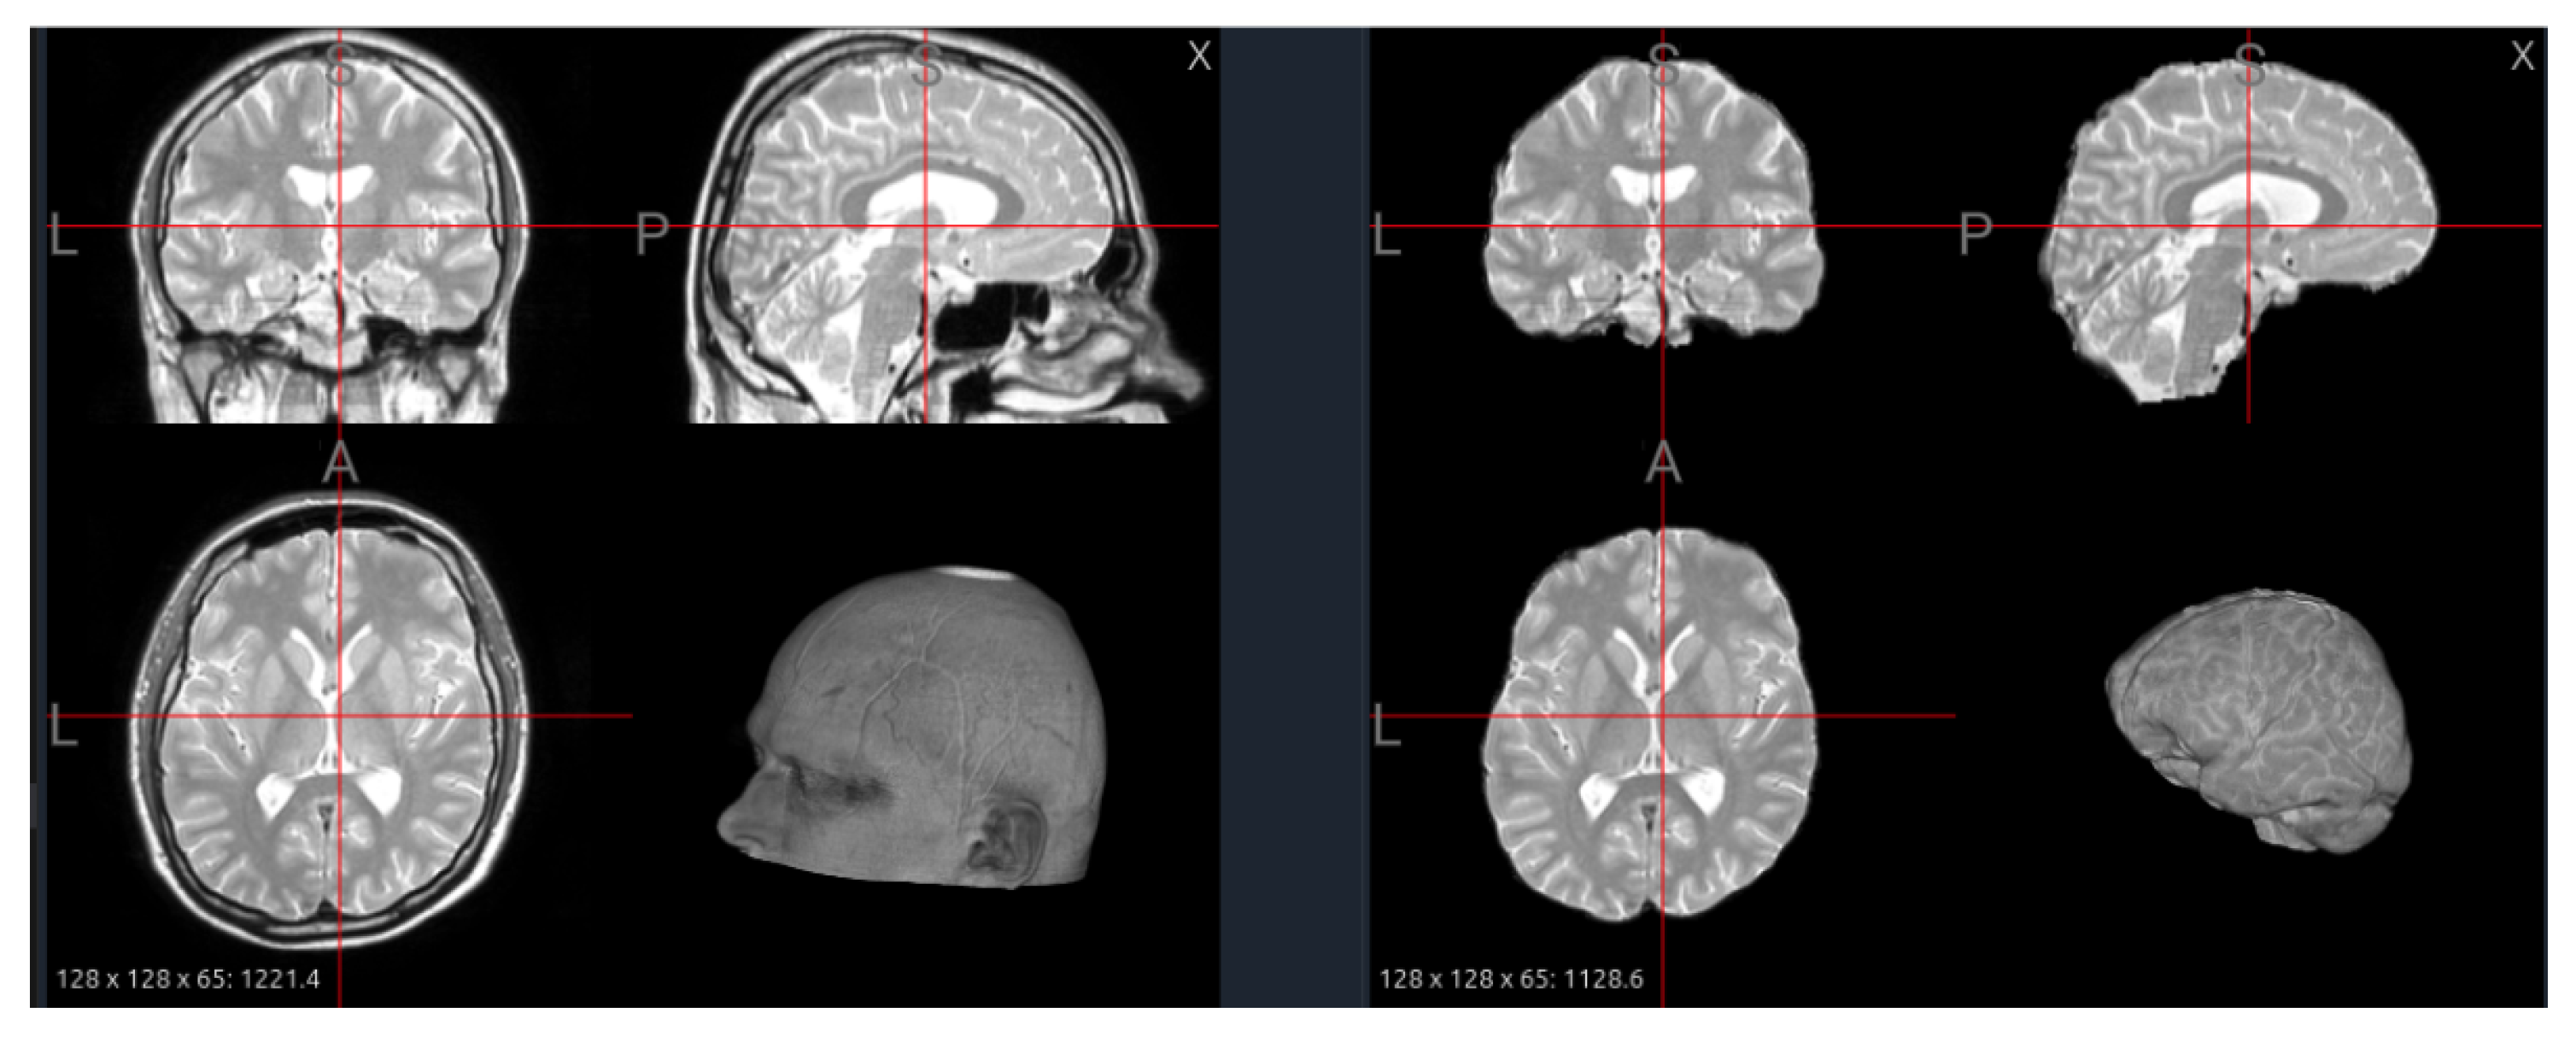

Intensity normalization is the process of adjusting MRI voxel values to a common scale so that images from different scanners or subjects become comparable. The most common techniques include z-score normalization, histogram matching, and WhiteStripe normalization. Z-score normalization rescales each image to have zero mean and unit variance, reducing intensity range differences; it is best used as a simple, general method when datasets are diverse or lack a consistent reference. Histogram matching aligns the intensity distribution of each image to that of a reference scan or template, making it ideal for multi-site datasets with large scanner or protocol variability. WhiteStripe normalization uses the intensity range of normal-appearing white matter to anchor scaling, which is most effective for brain studies where maintaining tissue contrast is important.

As summarized in Table 4, the original voxel intensities span a wide range, reflecting strong contrast between bright enhancement regions and darker tissues. After applying z-score normalization, the intensity distribution becomes centered around zero with reduced variance, resulting in a more uniform and balanced appearance across tissues. However, this transformation also alters the visual contrast, as shown in Figure 7: some brain regions appear brighter, while fine structural details become less pronounced. This effect occurs because z-score normalization rescales voxel values relative to the global mean and standard deviation, thereby compressing the overall dynamic range and reducing intensity extremes.

When building foundation models, intensity normalization should be applied consistently across all datasets to prevent artificial domain shifts. The chosen method must preserve relative tissue contrast while harmonizing global intensity ranges. It is also beneficial to expose the model to multiple normalization styles during pretraining, helping it learn invariance to contrast variations. Finally, combining preprocessing-based normalization with learnable normalization layers (e.g., instance or adaptive layer normalization) allows the model to adapt dynamically to unseen data while maintaining stable, harmonized feature representations.